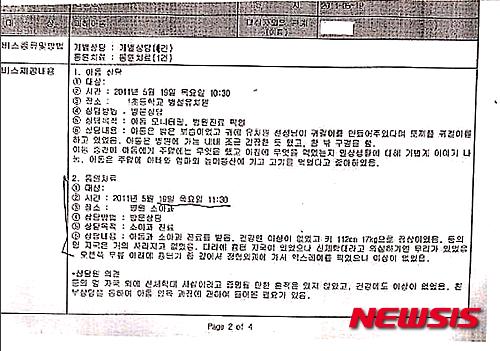

【서울=뉴시스】신정원 조명규 기자 = #1. (등의) 멍 자국이 생생했음. (중략) 아동은 수박을 먹으며 묻는 질문에 자연스럽게 대답함. 친모가 친부에 대해 부정적으로 대답한 것은 전혀 없었고, (중략) 친모와 친부 중에 누가 더 좋냐고 묻자 둘 다 좋다고 함. (중략) 아동에게 꿈이 뭐냐고 묻자 대답하지 못함. (후략)(2011년 5월13일)

#2. 이마에 난 상처는 왜 그런 것이냐고 묻자 집에서 의자에 받혔다고 함. (중략) 다른데 아픈 데는 없냐고 묻자 없다고 했으며 오늘 등이나 배가 아프다고 했는데 괜찮냐고 묻자 괜찮다고 함. '친모는 좋은 엄마야?' 하고 묻자 좋은 엄마라고 함. (중략) 친부랑은 뭐하고 놀았냐고 하자 '아빠랑 집에서 비행기 타다가 창문에 부딪혔어요'라고 함. (중략) 친모가 차가 있어서 유치원에 데리러 온다고 했으나 교사에게 확인해 보니 유치원 차로 아파트 근처까지 픽업하고 그 곳에서 친모가 아동을 데리고 간다고 함.(2011년 5월19일)

뉴시스가 확보한 상담일지는 총 3개다. 2011년 5월13일 방문상담 내용과 5월19일 방문상담 및 통원치료 내용이다.